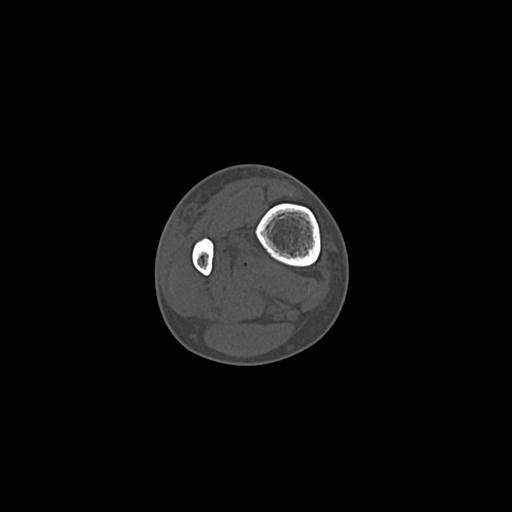

56476 8/28 4R 1/21 2R 左足関節 デジカメ写真 72歳女性 右足関節AS